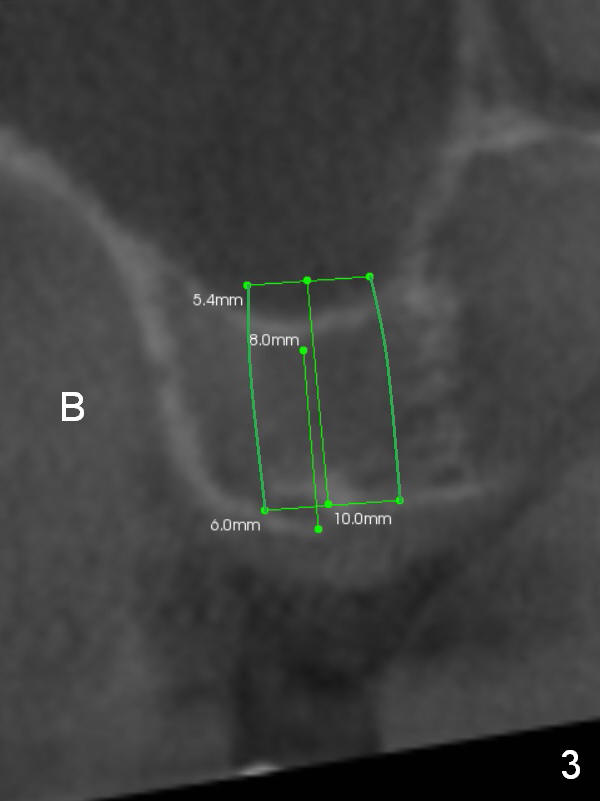

To handle the 2nd challenge, start bone expansion with #15 and osteotomes (from 8 to 11 mm). Set implant spacer at 4 mm (Fig.2). Prepare allograft (.5-1 mm) and Osteogen (4:1 ratio) for sinus lift. Place 8 mm stopper on the larger condenser from Sinus Master Kit.